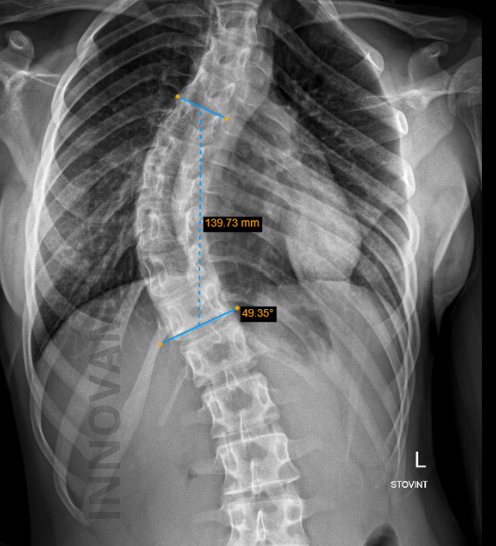

Rentgeno Tyrimas

Rentgeno tyrimas – tai pagrindinis diagnostinis metodas, leidžiantis išsamiai įvertinti stuburo būklę, ypač įtariant ar stebint skoliozę. Šis tyrimas yra ypač svarbus vaikystėje ir paauglystėje – augimo bei brendimo laikotarpiu, kai stuburas greitai vystosi ir skoliozės progresavimo rizika yra didžiausia.

- Tiksliai nustatyti stuburo iškrypimo laipsnį – tai daroma matuojant vadinamąjį Kobo kampą (Cobb angle), kuris leidžia objektyviai įvertinti skoliozės sunkumą.